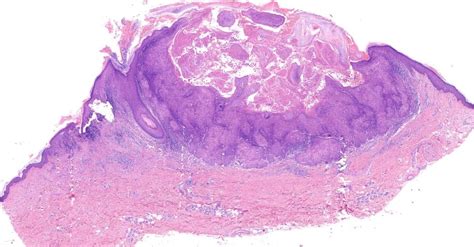

Sporotrichoid Nocardia

Dermatopathology Society of India: Image of the Month